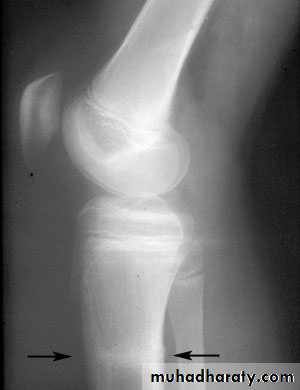

41Physeal injuries

10% of fractures in children

Salter - Harris classification:

1: separation of the epiphysis usually thru the calcified zone

2: separation of epiphysis & triangular piece of metaphysis

Wahby Ghalib

42

3: intra-articular # thru epiphysis then thru physis

4: intra-articular # thru epiphysis, physis, & metaphysis5: crushing of physis arrested growth

44# may not be visible initially

Types 1 & 2 : good Px except around the kneeTypes 3 & 4: need perfect reduction & f/u for re-displacement

45Complications

Arrested growth

Accelerated growth

Asymmetrical growth